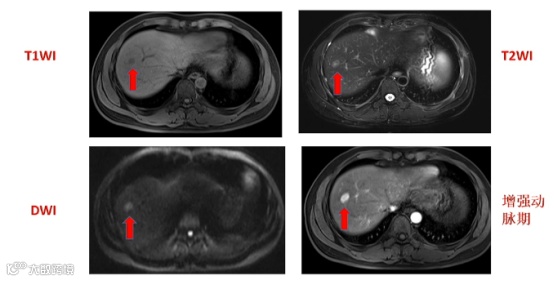

患者女性,63岁,甲胎蛋白升高。该病例若使用非边缘APHE+门脉期廓清将不能诊断为HCC,将移行期廓清纳入诊断标准后,则可以诊断为scHCC,且病理证实Edmondson-Steiner II级HCC。

a:T2WI高信号,b:DWI弥散受限,c:动脉期非环形强化,d:门脉期无明显廓清,e:过渡期低信号,f:移行期低信号,直径为7.3mm[5]。